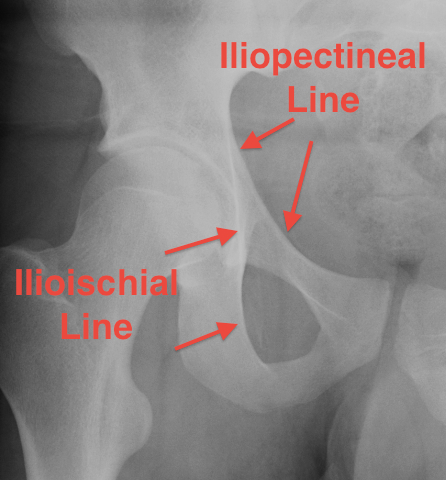

AP / Six X-ray Landmarks

1. Iliopectineal line

- along pelvic brim to pubic symphysis

- anterior column

2. Ilioischial Line

- pelvic brim to ischial tuberosity

- posterior column

- formed by posterior 4/5 of quadrilateral surface ilium